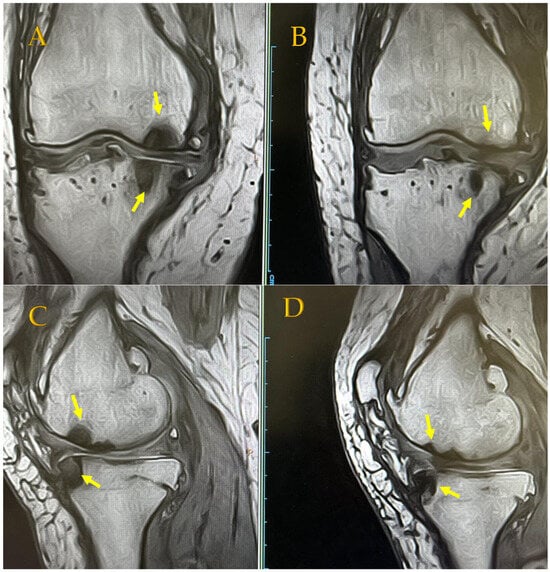

In addition, combined treatment may be expected to produce anti-inflammatory and cell proliferation effects, as seen on radiographs of the KL4 front-of-knee OA of a 64-year-old woman before APS therapy and 48 months after APS therapy. This patient continued ESWT approximately once or twice a month after the APS injection but showed a slight opening of the joint dehiscence compared with that before the APS injection (Figure 4). MRI of the same patient 48 months later showed the reduction in BML in T1 (upper photo), and the disappearance of bone cysts in T2 (lower photo) was confirmed (Figure 5). Since APS is a PRP product, it originally contains a large amount of TGFβ; however, the increased TGFβ level due to ESWT stimulation may have contributed to the anti-inflammatory effect and the regulation of cell proliferation and differentiation [,].

MRI findings of a KL4 64-year-old female patient. (A) BML and SBC on medial condyle Pre-APS therapy. (B) In T1 (upper photo), MRI after 4 years confirmed a reduction in BML, and in T2 (lower photo), the disappearance of bone cysts was confirmed. 8 October 2019 MRI T1 Pre-APS therapy (lt.) → 16 October 2023 MRI T1 4 years later after APS therapy (rt.); APS (31 October 2019) + ESWT 36 times (every 1–2 months) after APS therapy. (A) coronal view (18 October 2019) (B) coronal view (16 October 2023) (C) sagittal view (18 October 2019) (D) sagittal view (16 October 2023).